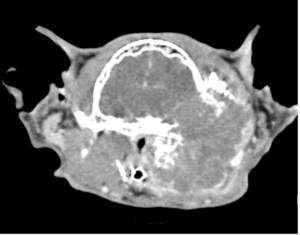

CT and MRI continue to gain traction as they become more widely available and less costly. Their diagnostic superiority over radiography will improve the treatment of some common diseases in small animal patients.